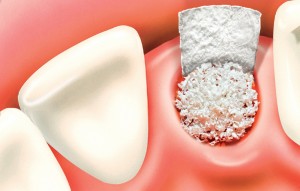

Остеопластика или «наращивание костной ткани» при имплантации — выбор метода и отдаленные результаты.

Cегодня я хотел бы показать вам одну работу, которую я начал более года назад. А заодно рассказать о ее нюансах. Вы знаете, что секретов у меня нет, поэтому буду рад вашим вопросам и ремаркам в комментариях